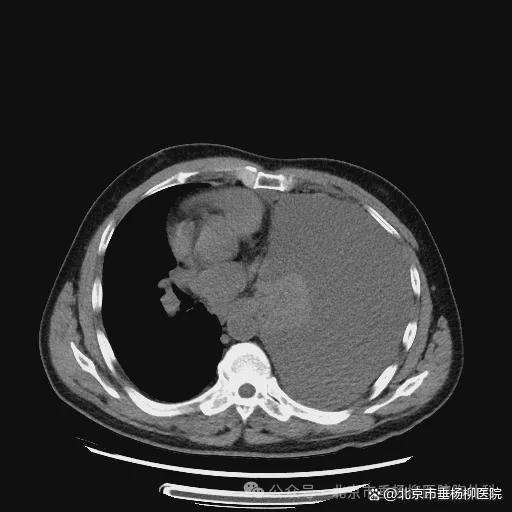

热灌注前